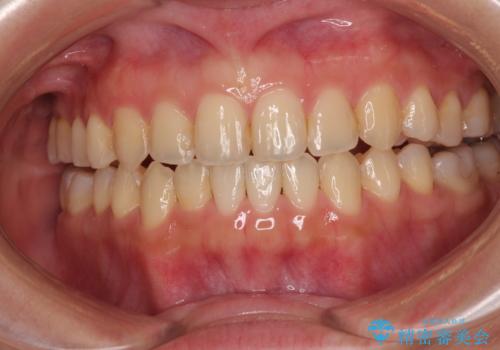

ウェディング前のホワイトニングとエアーフロー

担当医 歯科衛生士